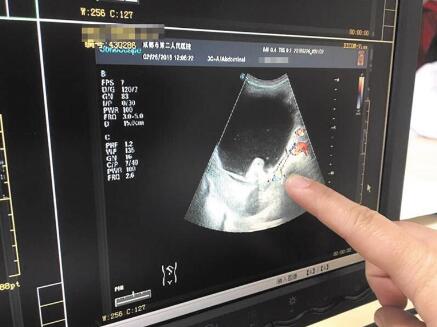

2月26日,何先生带着小月来到市二医院。“别人打B超都是很快就出来了,小月却在里面很久,我们当时就觉得情况有点严重。”何先生说。结果不出他所料,通过B超检查,医生发现小月的卵巢上有一个18.4×9厘米的巨大包块,怀疑是畸胎瘤,随后将小月转入妇科进一步检查、治疗。